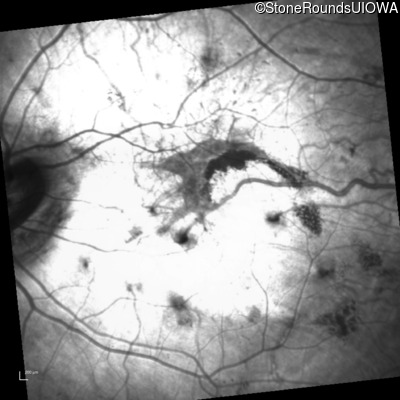

Infrared Fundus Photograph - Left - 20/25 -2

Exemplar